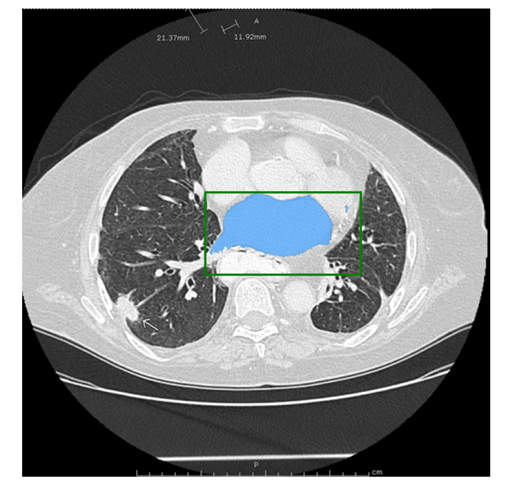

医学图像:

该图片是测试图片,从网站上下载的。